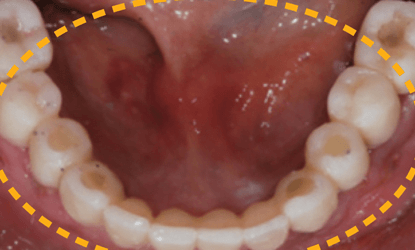

Vienmomentis funkcijos ir estetikos atstatymas

Vienmomentis krūminių dantų atstatymas laikinomis restauracijomis

Vienmomentis pilnas dantų atstatymas